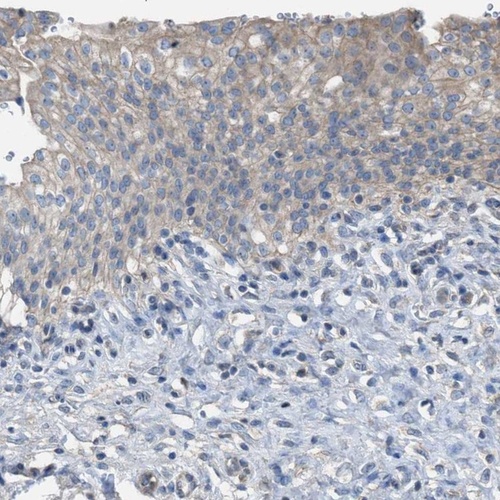

Immunohistochemistry analysis in human kidney and urinary bladder tissues using HPA021332 antibody. Corresponding NQO2 RNA-seq data are presented for the same tissues.